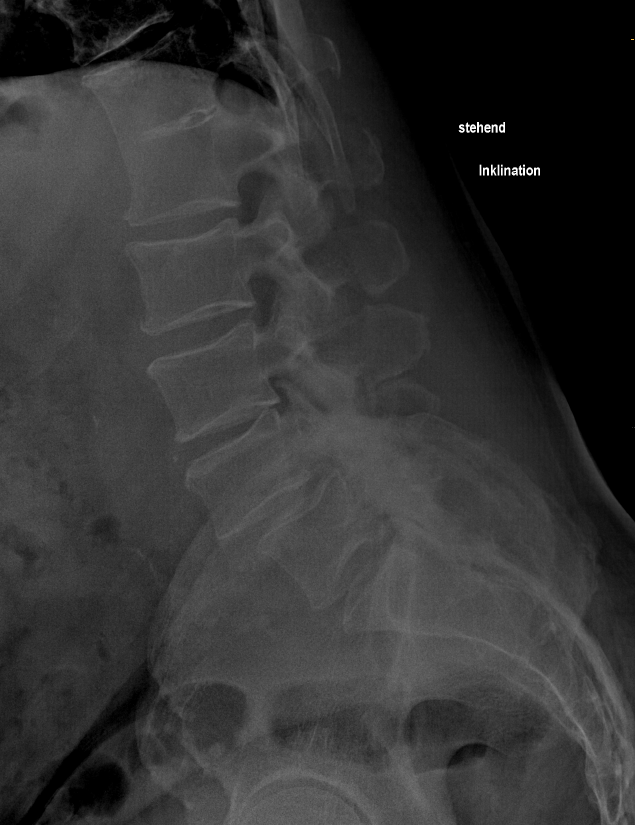

Inklination der LWS

Seitliches Röntgenbild der Lendenwirbelsäule bei einer Inklinationsbewegung.